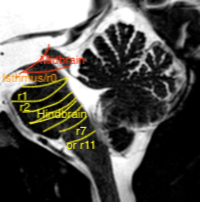

Historically the divisions of the brain stem are based on the morphology. The middle part connecting to the cerebellum was named pons, with a “pregnant belly” on sagittal images. The upper part “for the eye movements” is the midbrain and the part below the pons is the medulla oblongata.

Figure 1 Brain stem divisions and cerebellum on sagittal T2 weighted image of the posterior fossa

In gestational week 5-6 the cephalic, pontine and cervical flexure appear in the neural tube, displacing the alar plates laterally. The laterally displaced alar plates line a diamond (rhomboid) shaped membranous area and form the rhombic lips, subdivided in rhombomeres. From these rhombic lips, more specifically the rostral rhombomere r1, the cerebellar hemispheres are formed covering the upper part of the rhomboid membranous area, “closing” from superolateral like the curtains at the opera. The cerebellum has two germinal matrices: glutamatergic cells from the rhombic lips, and GABAergic Purkinje cells from the ventricular zone (23).